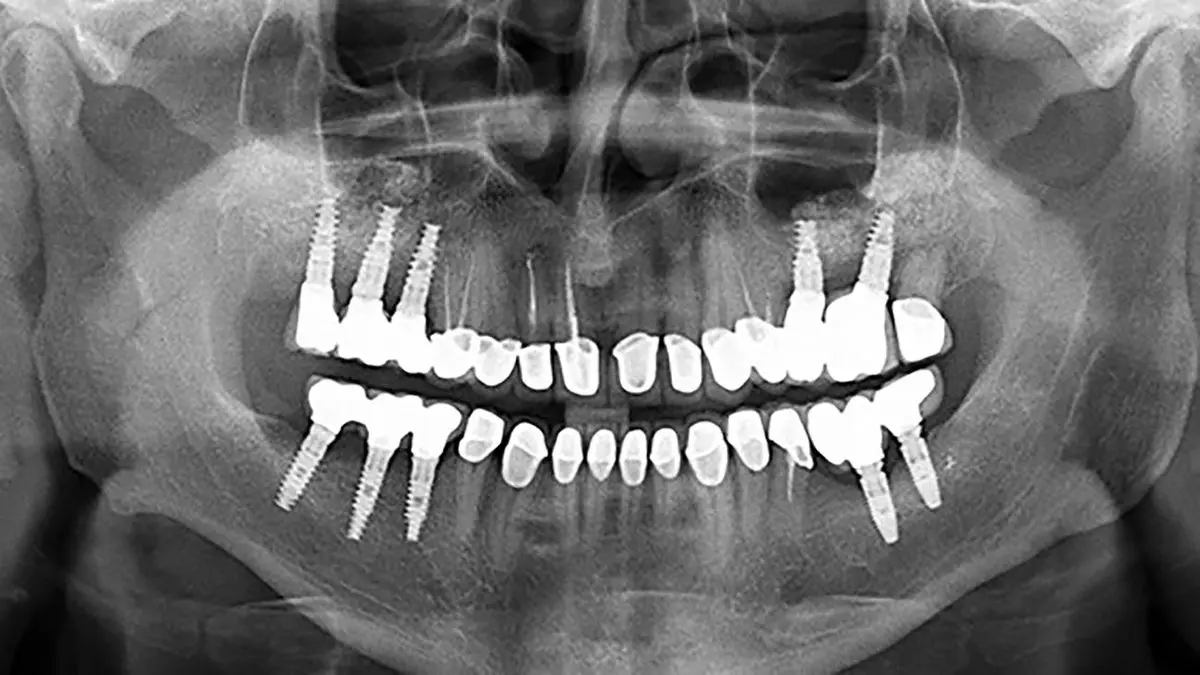

رکنا: متخصص رادیولوژی و عضو هیات علمی دانشگاه علوم پزشکی کردستان اذعان کرد که اهمیت تصویربرداری در فرآیند درمان دندانپزشکی به ویژه در زمینه طراحی و قرار دادن ایمپلنتها بسیار مهم است.

به گزارش رکنا، دکتر نغمه نصراللهی با اشاره به اهمیت دقت در تصویربرداری افزود: تصویربرداری دقیق از صورت بیمار برای اندازه گیریهای صحیح و پیش بینیپذیری در درمان ضروری است که این دقت به انتخاب مدالیته مناسب برای ارزیابی ناحیه قبل از جراحی بستگی دارد.

وی بیان کرد: استفاده از تکنیکهای تصویربرداری سه بعدی (CBCT) به دلیل توانایی در ارائه جزئیات دقیقتر از ساختارهای استخوانی و بافتهای نرم، نسبت به روشهای دو بعدی برتری دارد که این تکنیک امکان مشاهده لایههای مختلف و اندازهگیری دقیقتر را فراهم میکند.

نصراللهی افزود: در صورت عدم دقت در تصویربرداری، مشکلاتی نظیر جابجایی ایمپلنت ، خونریزی و درد شدید بیمار ممکن است رخ دهد. بنابراین توجه به جزییات و دقت در اندازهگیریها ضروری است.

وی ادامه داد: تکنیک CBCT به دلیل توانایی در ارائه جزییات بالاتر و دقت بیشتر در اندازهگیریهای استخوانی، به عنوان ابزاری مؤثر در طراحی درمانهای دندانپزشکی شناخته میشود.

وی ادامه داد: در فرآیند طراحی ایمپلنت، توجه به فاصله ایمپلنتها از ساختارهای حیاتی و جلوگیری از آسیب به آنها از اهمیت بالایی برخوردار است.

متخصص رادیولوژی افزود: ترکیب تصاویر مختلف برای تولید یک تصویر جامع و دقیق از ناحیه درمانی، به منظور طراحی بهتر و جلوگیری از خطاهای احتمالی، مورد تأکید قرار می گیرد.